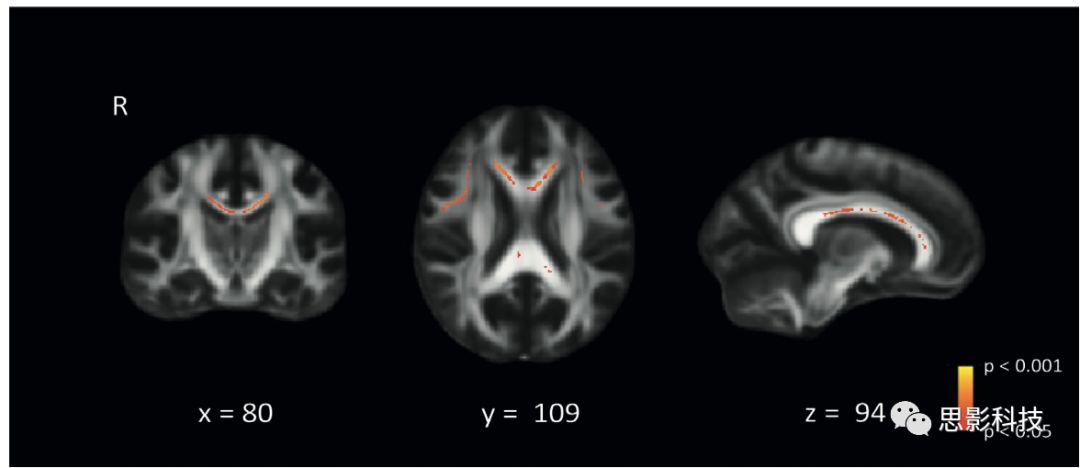

1、表2呈現(xiàn)了基線人口學(xué)信息以及神經(jīng)影像特征隨時(shí)間的變化?;€時(shí)被試平均年齡為68(SD 8.0), 平均隨訪時(shí)間為3.4年(SD 0.2, 隨訪時(shí)間在兩個(gè)WMH組間大致相同。對于所有被試,認(rèn)知加工速度皆出現(xiàn)隨時(shí)間的下降。在基線時(shí)段,重度WMH組的FA值明顯比輕中度WMH組要低,主體現(xiàn)在胼胝體,尤其是胼胝體膝和額葉p<0.05, FWE校正)

2. 輕中度WMH組與重度WMH組之間FA值的比較 (雙樣本T檢驗(yàn),p<0.05,經(jīng)過多重比較校正;回歸了年齡、性別、SVD經(jīng)典標(biāo)記等;結(jié)果疊加在MNI T1標(biāo)準(zhǔn)腦上)。

(2)輕重度WMH組和重度WMH組在彌散指標(biāo)(FA等)上存在明顯差別,主要體現(xiàn)在連通左右腦的胼胝體(因此影響了全腦網(wǎng)絡(luò)的連通性?)